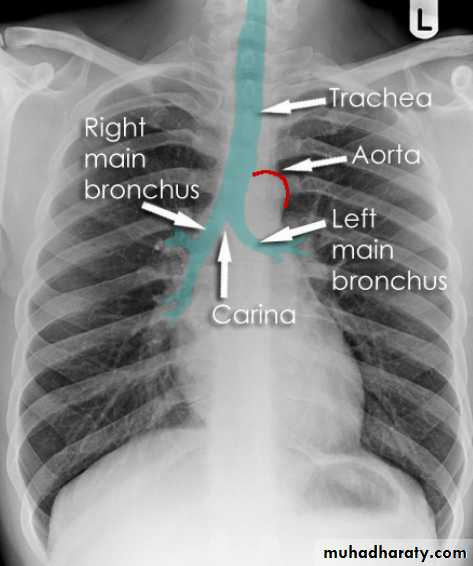

Hilar structuresThe hila (lung roots) are complicated structures mainly consisting of the major bronchi and the pulmonary veins and arteries. These structures pass through the narrow hila on each side and then branch as they widen out into the lungs. The hila are not symmetrical but contain the same basic structures on each side.

Each hilum contains major bronchi and pulmonary vessels

There are also lymph nodes on each side(not visible unless abnormal)

The left hilum is often higher than the right

Both hila should be of similar size and density. If either hilum is bigger and more dense, this is a good indication that there is an abnormality.

Lung markings reflects pulmonary vasculature